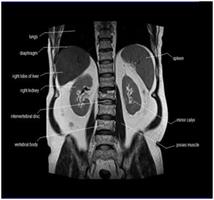

Your doctor has ordered a MRI (Magnetic Resonance Imaging) of your abdomen. MRI uses a magnetic field, radio waves, and a computer to create images soft tissues, bones, and internal body structures. MRI of the abdomen allows physicians to examine the abdominal anatomy to rule out any structural abnormalities.

MRI of the Abdomen1   MRI of the Abdomen2MRI of the Abdomen3